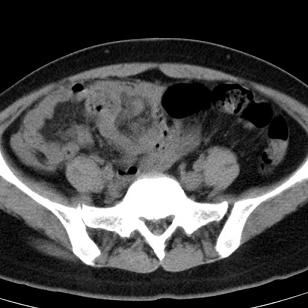

标题: CT19559:子宫及附件正常吗?

女,35岁,反复下腹部隐痛数月。

感觉上,子宫好象大了点

如果未孕,子宫体稍大,宫腔增宽,附件区未见异常密度影,还是建议结合b超检查为好,ct平扫对妇科没有优势。

子宫弥漫性等密度肿大,宫腔内缘见结节影突入腔内,子宫内膜异位可能